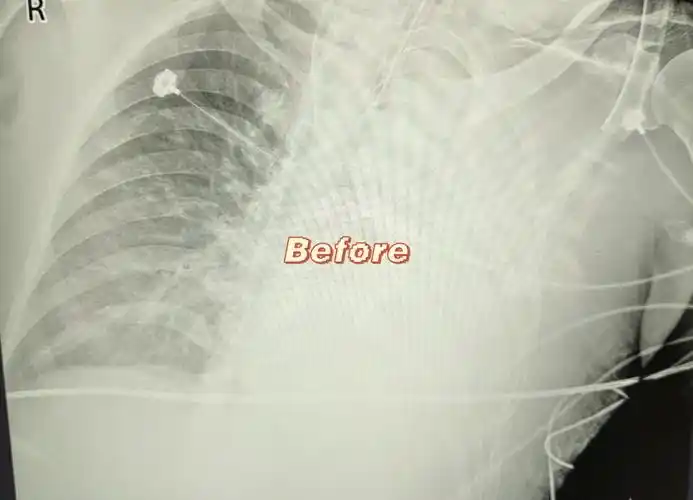

双肺胸片